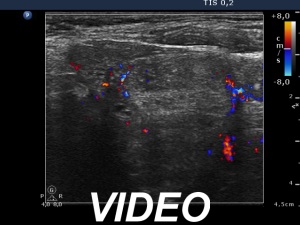

Ultrasonography. The thyroid was minimally hypoechogenic and had multiple discrete lesions which were mostly echonormal. The thyroid had a pseudonodular pattern. There were several hypoechogenic discrete areas.